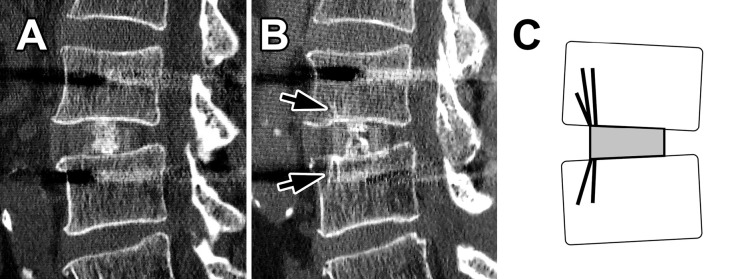

Results: TBR was commonly observed anterior to the cage on CT sagittal images. The TBR-positive rate was 21%, 67%, and 73% at 3 months, 1 year, and 2 years postoperatively, respectively. The 3-month TBR-positive segments showed significantly less VEC (0% vs. 29%, P=0.029) at 1 year postoperatively. The 1-year TBR-positive segments showed a significantly higher facet union rate (83% vs. 57%, P=0.019) and less pseudoarthrosis (0% vs. 13%, P=0.041) at 2 years postoperatively. At 5 years postoperatively, 50% of the 2-year TBR-positive segments turned negative with solid intervertebral bony fusion.

Conclusions: TBR-positive segments had significantly lower future VEC positivity, higher future facet union rates, and lower future pseudarthrosis rates. In LLIF-PSF, TBR suggests the establishment of intervertebral stability and allows consideration of intervertebral biomechanics.